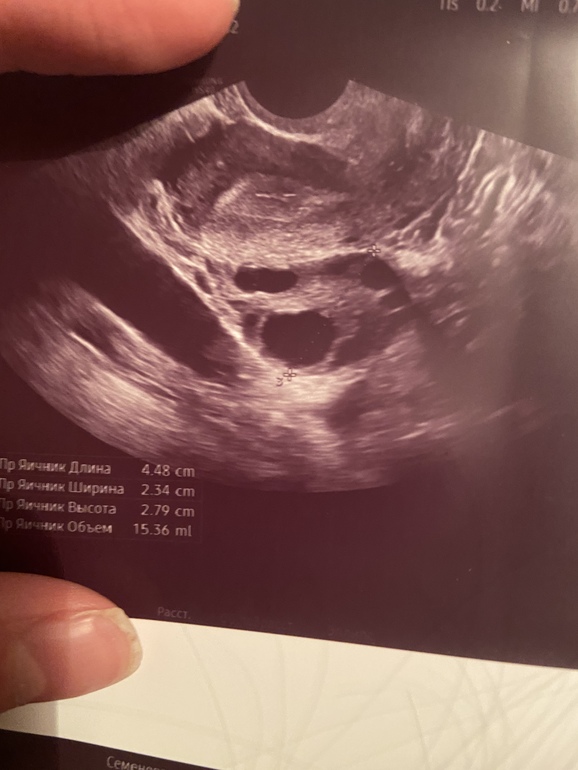

Так это правда. Я долго лазила и искала ответ, почему ДФ квадратный, яйцеобразный и пр. Оказалось, это именно в момент О он вытягивается, лопается и стенки опадают, делаясь многоугольным, квадратными, складчатым...пока не начнёт заполняться капиллярами и лютеином, тогла и станет ЖТ. Вот именно в момент выпуска на свободу ЯК мы и поймали на УЗИ! Он уже пуст был! Жаль не видно, как головастики насилуют ЯК🤭

Вот что мне ответили на другом сайте, показала фото с УЗИ этого квадратного нечто.

Ещё раз посмотрела вообще узи. Да у вас на ЖТ намного больше похоже! Смотрю на свой и он все таки круглый такой , непонятно мне , хотя бы квадратный и как будто с дырочкой по контуру.

хотя смотрю все таки рваные немного края